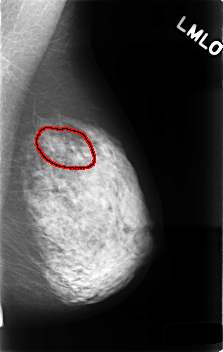

C_0495_1.LEFT_MLO

LEFT_MLO LINES 4568 PIXELS_PER_LINE 2888 BITS_PER_PIXEL 12 RESOLUTION 50 OVERLAY

FILE: C_0495_1.LEFT_MLO.OVERLAY

TOTAL_ABNORMALITIES 1

ABNORMALITY 1

LESION_TYPE CALCIFICATION TYPE AMORPHOUS DISTRIBUTION SEGMENTAL

ASSESSMENT 4

SUBTLETY 2

PATHOLOGY BENIGN

TOTAL_OUTLINES 1

BOUNDARY